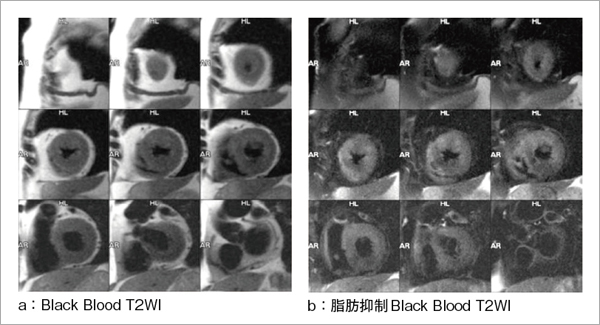

心臓疾患のCTとMRI 第2版 | 書籍詳細 | 書籍 | 医学書院。心臓疾患のCTとMRI 第2版 | 佐久間肇, 陣崎雅弘, 北川覚也, 石田。心臓血管疾患のMDCTとMRI | 書籍詳細 | 書籍 | 医学書院。ツインバード 低糖質ブランパンミックス&低糖質食パンミックス 糖質80%OFF。中央放射線部|川崎医科大学総合医療センター。書き込み、マーカーありません。心臓疾患のCTとMRI 第2版 | 書籍詳細 | 書籍 | 医学書院。【豊富な図解】多くの図や写真が掲載されており、視覚的に理解しやすい構成になっています。心臓疾患のCTとMRI 第2版 | 書籍詳細 | 書籍 | 医学書院。心臓疾患の診断に携わる医療専門家にとって、必携の一冊です。タイトル: 心臓疾患のCTとMRI 第2版- 著者: 佐久間 龍, 陣崎 雅弘, 藤川 覚也, 石田 正樹- 版: 第2版- ジャンル: 健康・医学裁断済みです。心臓血管CT・MRI図鑑 加地 修一郎(編集) - 文光堂 | 版元ドットコム。心臓疾患のCTとMRI 第2版 | 佐久間肇, 陣崎雅弘, 北川覚也, 石田。【専門的な内容】本書は心臓疾患に特化したCTおよびMRIの診断技術を詳細に解説しています。医療従事者や研究者にとって、心臓の画像診断に関する最新の知識を得るための重要なリソースです。心臓MRI最新技術 - 東芝メディカルシステムズ株式会社 - inNavi。心臓MRIについてのご説明 | 和歌山画像診断センター。実際の症例を通じて、診断のポイントを学ぶことができます。【実践的なアプローチ】臨床での応用を重視した内容で、実際の診断に役立つ情報が豊富に含まれています。症例6:診断と解説。心臓MRI最新技術 - 東芝メディカルシステムズ株式会社 - inNavi。